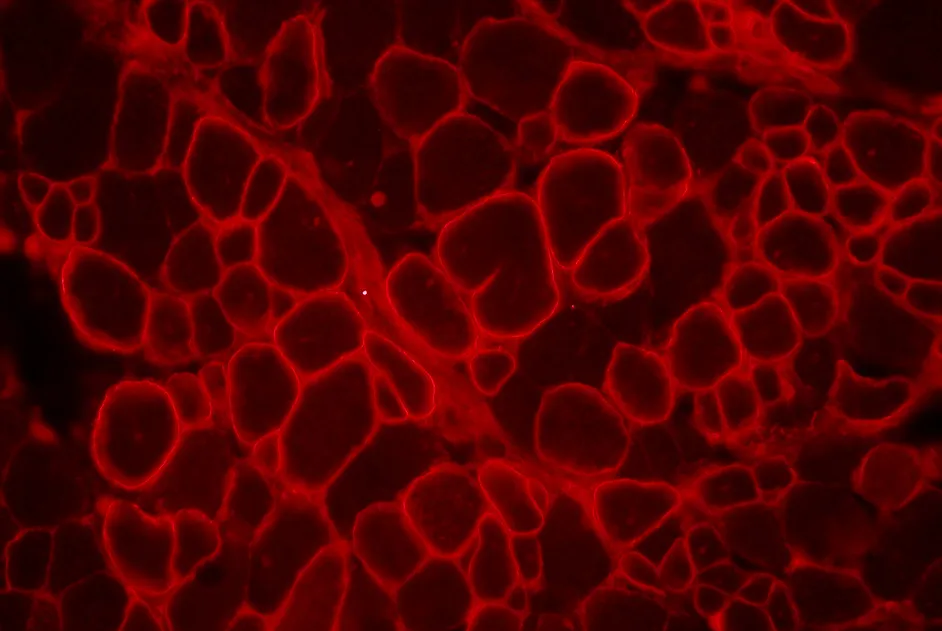

Les anticorps anti-MuSK dans la myasthénie auto-immune bloquent l’interaction de MuSK avec LRP4 et empêchent le regroupement des récepteurs de l'acétylcholine.